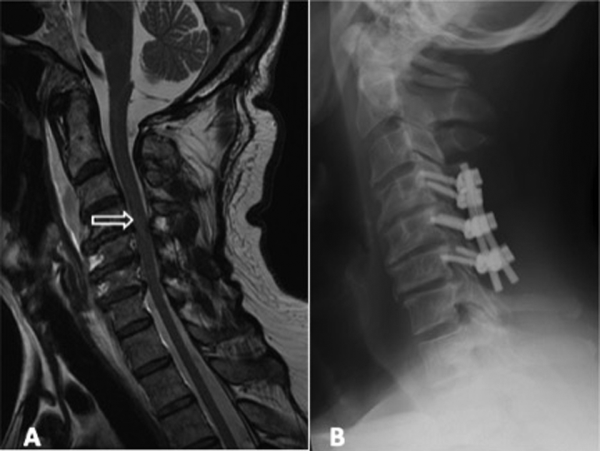

A 65-year-old male who fell down from a flight of stairs sustained a central cord syndrome. A, Sagittal T2 weight magnetic resonance imaging (MRI) demonstrating cervical stenosis and cord signal change (arrow). B, Lateral radiograph demonstrating the C4 to C6 posterior spinal fusion and laminectomy. The patient underwent for the management of his incomplete spinal cord injuries (SCI).